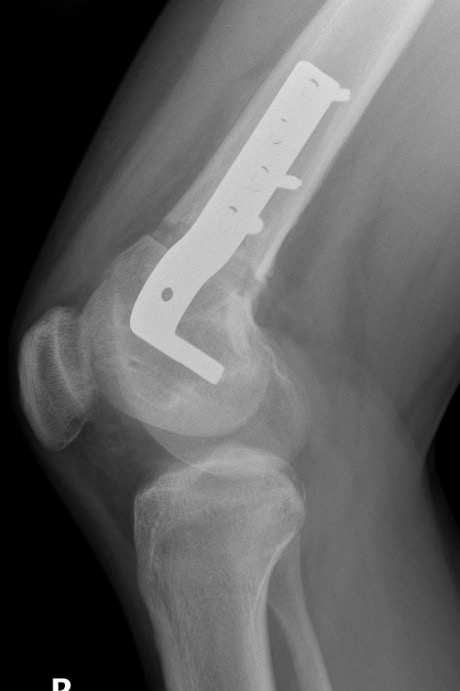

Salter Harris Type II with large Thurston Holland fragement

Distal Femur Salter Harris 2Distal Femur Salter Harris 2

Technique

AO foundation screw fixation Salter Harris Type II

Reduction

- attempt closed

- may be periosteum blocked on tension / medial side

Medial subvastus approach to knee

- identify Thurston-Holland fragment

- physeal sparing metaphyseal screws

Distal Femur SH2 ORIFDistal Femur SH2 ORIFDistal Femur SH2 Lateral